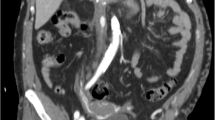

#CLTI , 82y/o , DM occlusion of ATA and PTA , heavy calcium and small arteries. #revascularization ✅ of foot arch through ATA , limb saved from #amputation #endovascular #interventional #diabeticfoot

banderaldhafery's tweet image. #CLTI , 82y/o , DM

occlusion of ATA and PTA , heavy calcium and small arteries.

#revascularization ✅ of foot arch through ATA , limb saved from #amputation